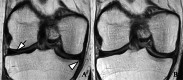

Methods: Participants with baseline opioid use (n=181) and who continued use for ≥1 year between baseline and 4-year follow-up (n=79) were included from the Osteoarthritis Initiative cohort and frequency matched with non-users (controls) (1:2). Whole-Organ Magnetic Resonance Imaging Scores (WORMS) were obtained, including a total summation score (WORMS total, range 0-96) and subscores for cartilage (0-36), menisci (0-24), and bone marrow abnormalities and subchondral cyst-like lesions (0-18, respectively). Knee Injury Osteoarthritis Outcomes score (KOOS) symptoms, quality of life (QOL), and pain were also obtained at baseline and follow-up (range 0-100; lower scores indicate worse outcomes). Using linear regression models, associations between baseline and longitudinal findings were investigated. As pain may modify observations, a sensitivity analysis was performed for longitudinal findings. All analyses were adjusted for sex, BMI, age, race, and Kellgren-Lawrence grade.

Results: Opioid users had greater structural degeneration at baseline (WORMS total: Coef. [95% CI], P; 7.1 [5.5, 8.8], <0.001) and a greater increase over 4 years (4.7 [2.9, 6.5], <0.001), compared to controls. Cartilage and meniscus scores increased greater in opioid users, compared to controls (P≤0.001), and findings withstood the adjustment for baseline pain (P≤0.002). All baseline KOOS scores were lower in opioid users compared to controls (P<0.001). QOL loss was greater, when adjusted for baseline KOOS pain (QOL -6.9 [-11.6, -2.1], 0.005).